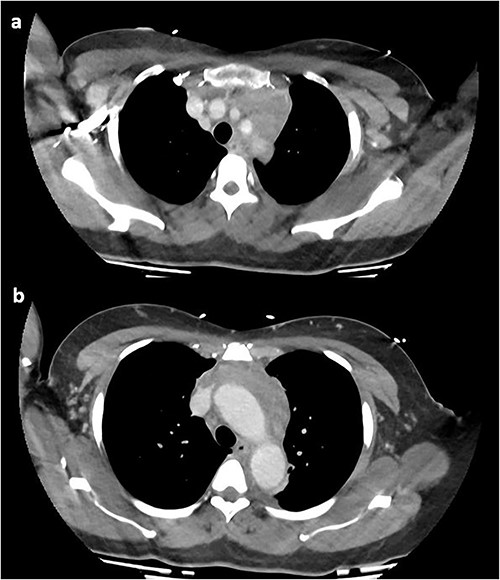

On repeat review of the CTPA, imaging was deemed atypical for acute aortic syndrome. A CT aortogram with delayed phase was performed, which demonstrated a 66-mm upper anterior mediastinal soft tissue density compressing the left brachiocephalic vein, as seen in Fig. 2.

CT chest with contrast demonstrating anterior mediastinal soft tissue density in the (a) upper chest and (b) lower chest.

At this time, the mass was suspicious for a malignancy, possibly a thymoma, lymphoma or germ cell tumour. All serum tumour markers (AFP, CEA, CA19-9, CA125) were negative. FDG-PET demonstrated that the anterior mediastinal density had moderate FDG update and no other avid lesions elsewhere. After multidisciplinary discussion, the mediastinal density was thought to most likely represent left brachiocephalic venous thrombophlebitis. A dedicated computed tomography (CT) venogram was performed, demonstrating extensive UEDVT from the left internal jugular vein extending into the left brachiocephalic and subclavian veins, seen in Fig. 3.

CT venogram demonstrating UEDVT in left brachiocephalic vein in the (a) upper chest and (b) lower chest.